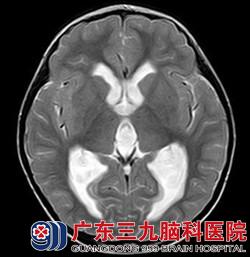

经华刚医生详细询问病史及查体后,明确患儿目前左侧小脑半球存在占位性病变。根据患者年龄结合头颅磁共振,考虑髓母细胞瘤可能性大,且病变已形成小脑扁桃体下疝,体征上已有不能走一字步,指鼻不准确、双手快速轮替运动差等症状。若肿瘤进一步生长,患者上述功能将进一步变差,甚至肿瘤严重压迫脑干,造成心跳呼吸骤停等风险。另外,因脑脊液循环通路因受肿瘤压迫,脑室内的脑脊液不能按正常途径回流,造成脑室内脑脊液过多、渗出,常常出现胡言乱语、大小便失禁、呕吐、精神反应变差等症状。患者需尽快行手术治疗,否则后果不堪设想。

看着生病的女儿情况一天比一天糟,小茹的父母心如刀割,但几万元的手术费用对一个务农的家庭来说是笔大数目。是放弃还是手术,小茹的父母内心苦苦挣扎着。在亲戚朋友劝说及帮助下,小茹父母终于筹到手术费用,为小茹办理了入院手续。接下来,医生们为小茹进行了“左侧小脑占位病变切除术+右额脑室外钻孔引流术”,术程顺利。术后病理示:髓母细胞瘤 WHO IV级。